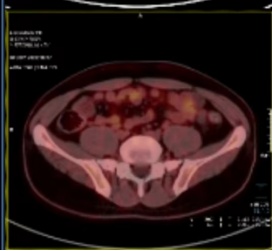

疗效评估:

2022-07至2022-10:

化疗方案:替吉奥60mg bid d1-14(q3w×4周期)

系统治疗后评估肿瘤退缩明显,经我院胃肠肿瘤MDT讨论并与患者及家属沟通后认为治疗有效,目前具备手术切除条件,拟再次手术治疗。